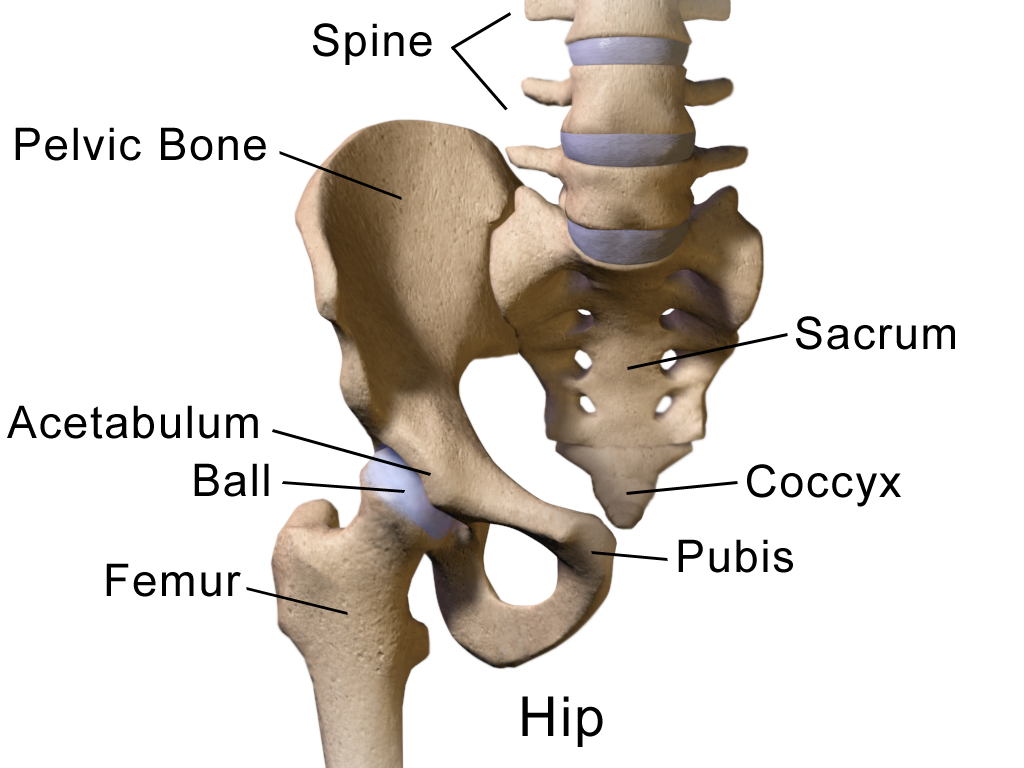

DXA可以檢查身體任何部位的骨密度,但最常用來檢查髖骨以及腰椎的骨密度。

若以上兩個部位因骨折而無法接受測量,醫師會測量側前臂橈骨(distal radius)的骨密度。

髖關節 |

BruceBlaus, CC BY 3.0 <https://creativecommons.org/licenses/by/3.0>, via Wikimedia Commons |

1. 股骨頸骨密度 T值 (股骨頸位於髖關節)